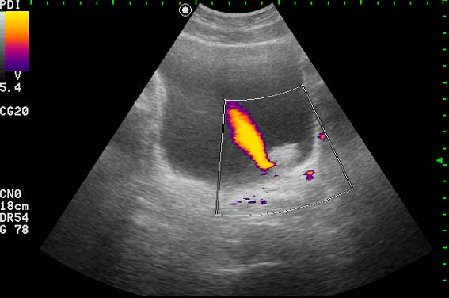

Находка у мужчины 65 лет

Ну конечно же, на представленных эхограммах - папиллярная опухоль мочевого пузыря.

Писать в заключении, что это полип - нельзя, это случай при котором руководствуются правилом - считаем опухоль злокачественной, пока не доказано обратное. Опухоль расположена над устьем левого мочеточника, нет обструкции устья и терминального отдела мочеточника (доказательство - наличие полноценного выброса мочи из устья) - что, в свою очередь, говорит против интралюминальной уретеральной опухоли.